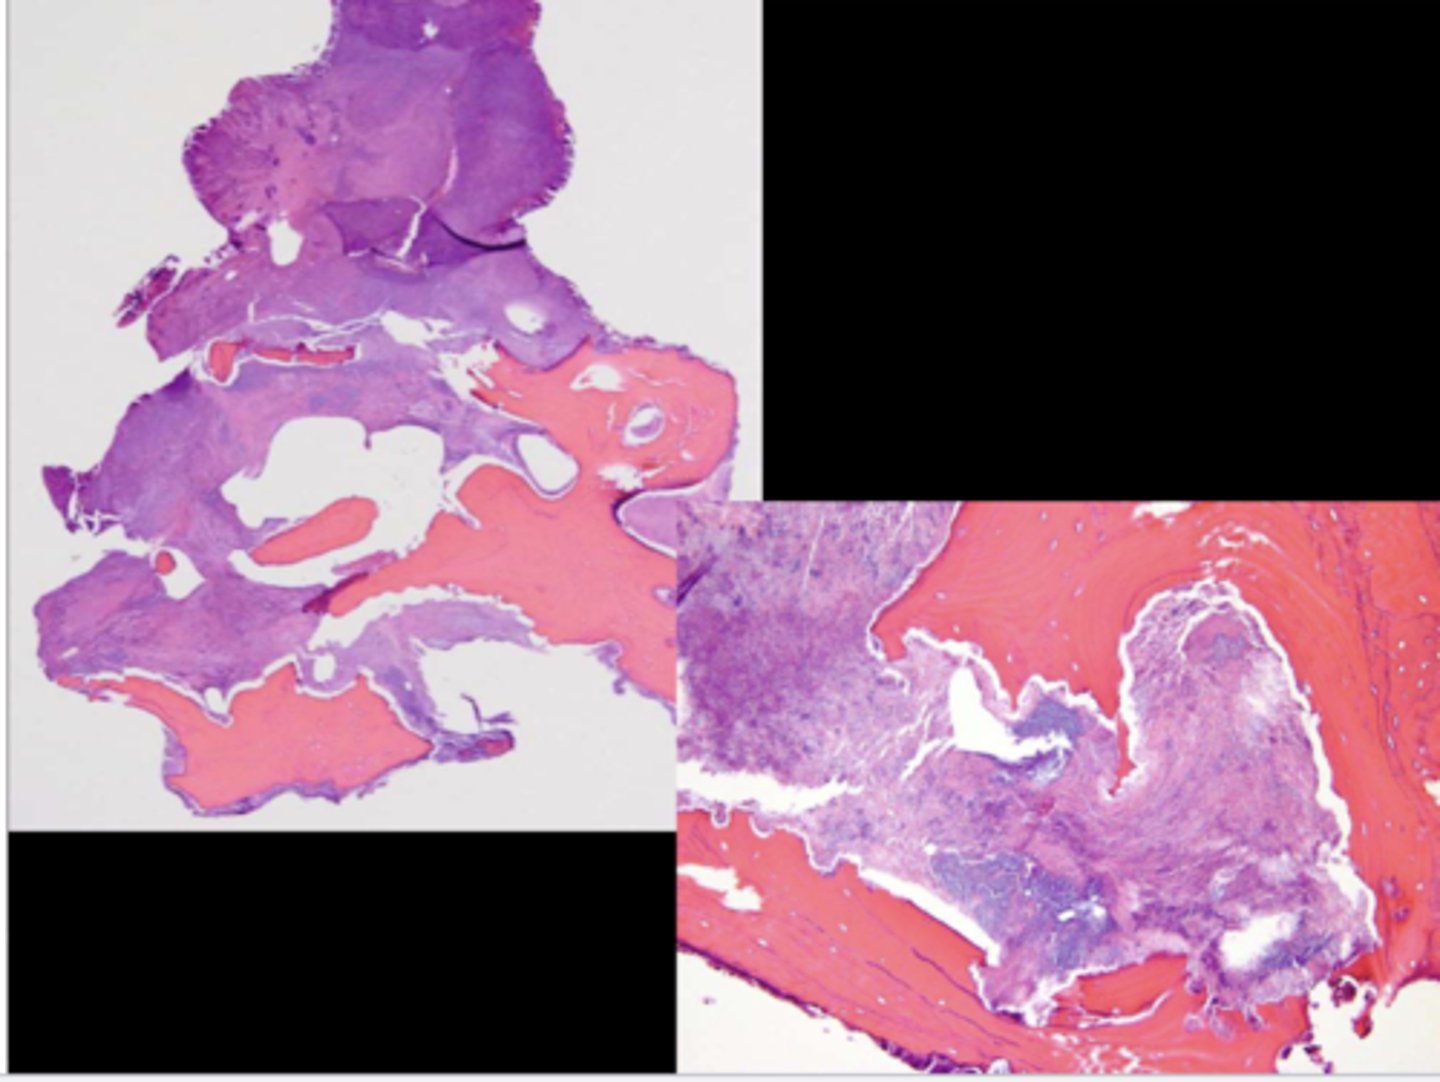

This is a histological image of what?

MRONJ